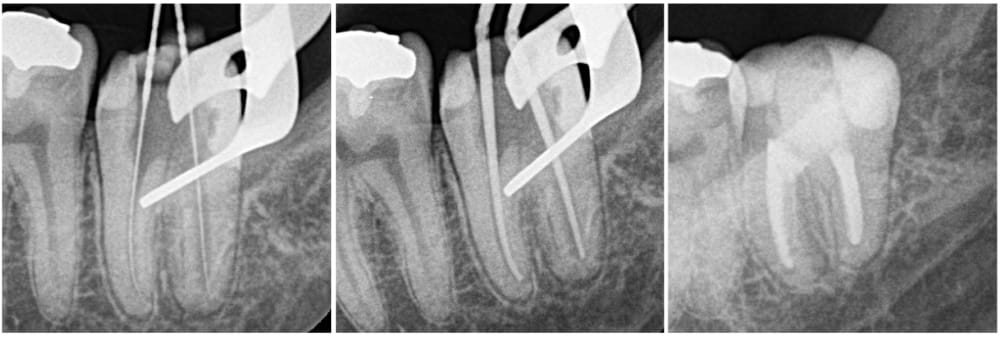

深い虫歯部分を除去し、電気メスにて止血後隔壁を作製し、根管治療を開始しました。

ラバーダム防湿下で、1回法にて治療を完了しています。

| 拡大号数 | M根・D根 #60/02 |

| 根管充填 | バイオセラミックシーラーを用いたHydraulic condensation technique |